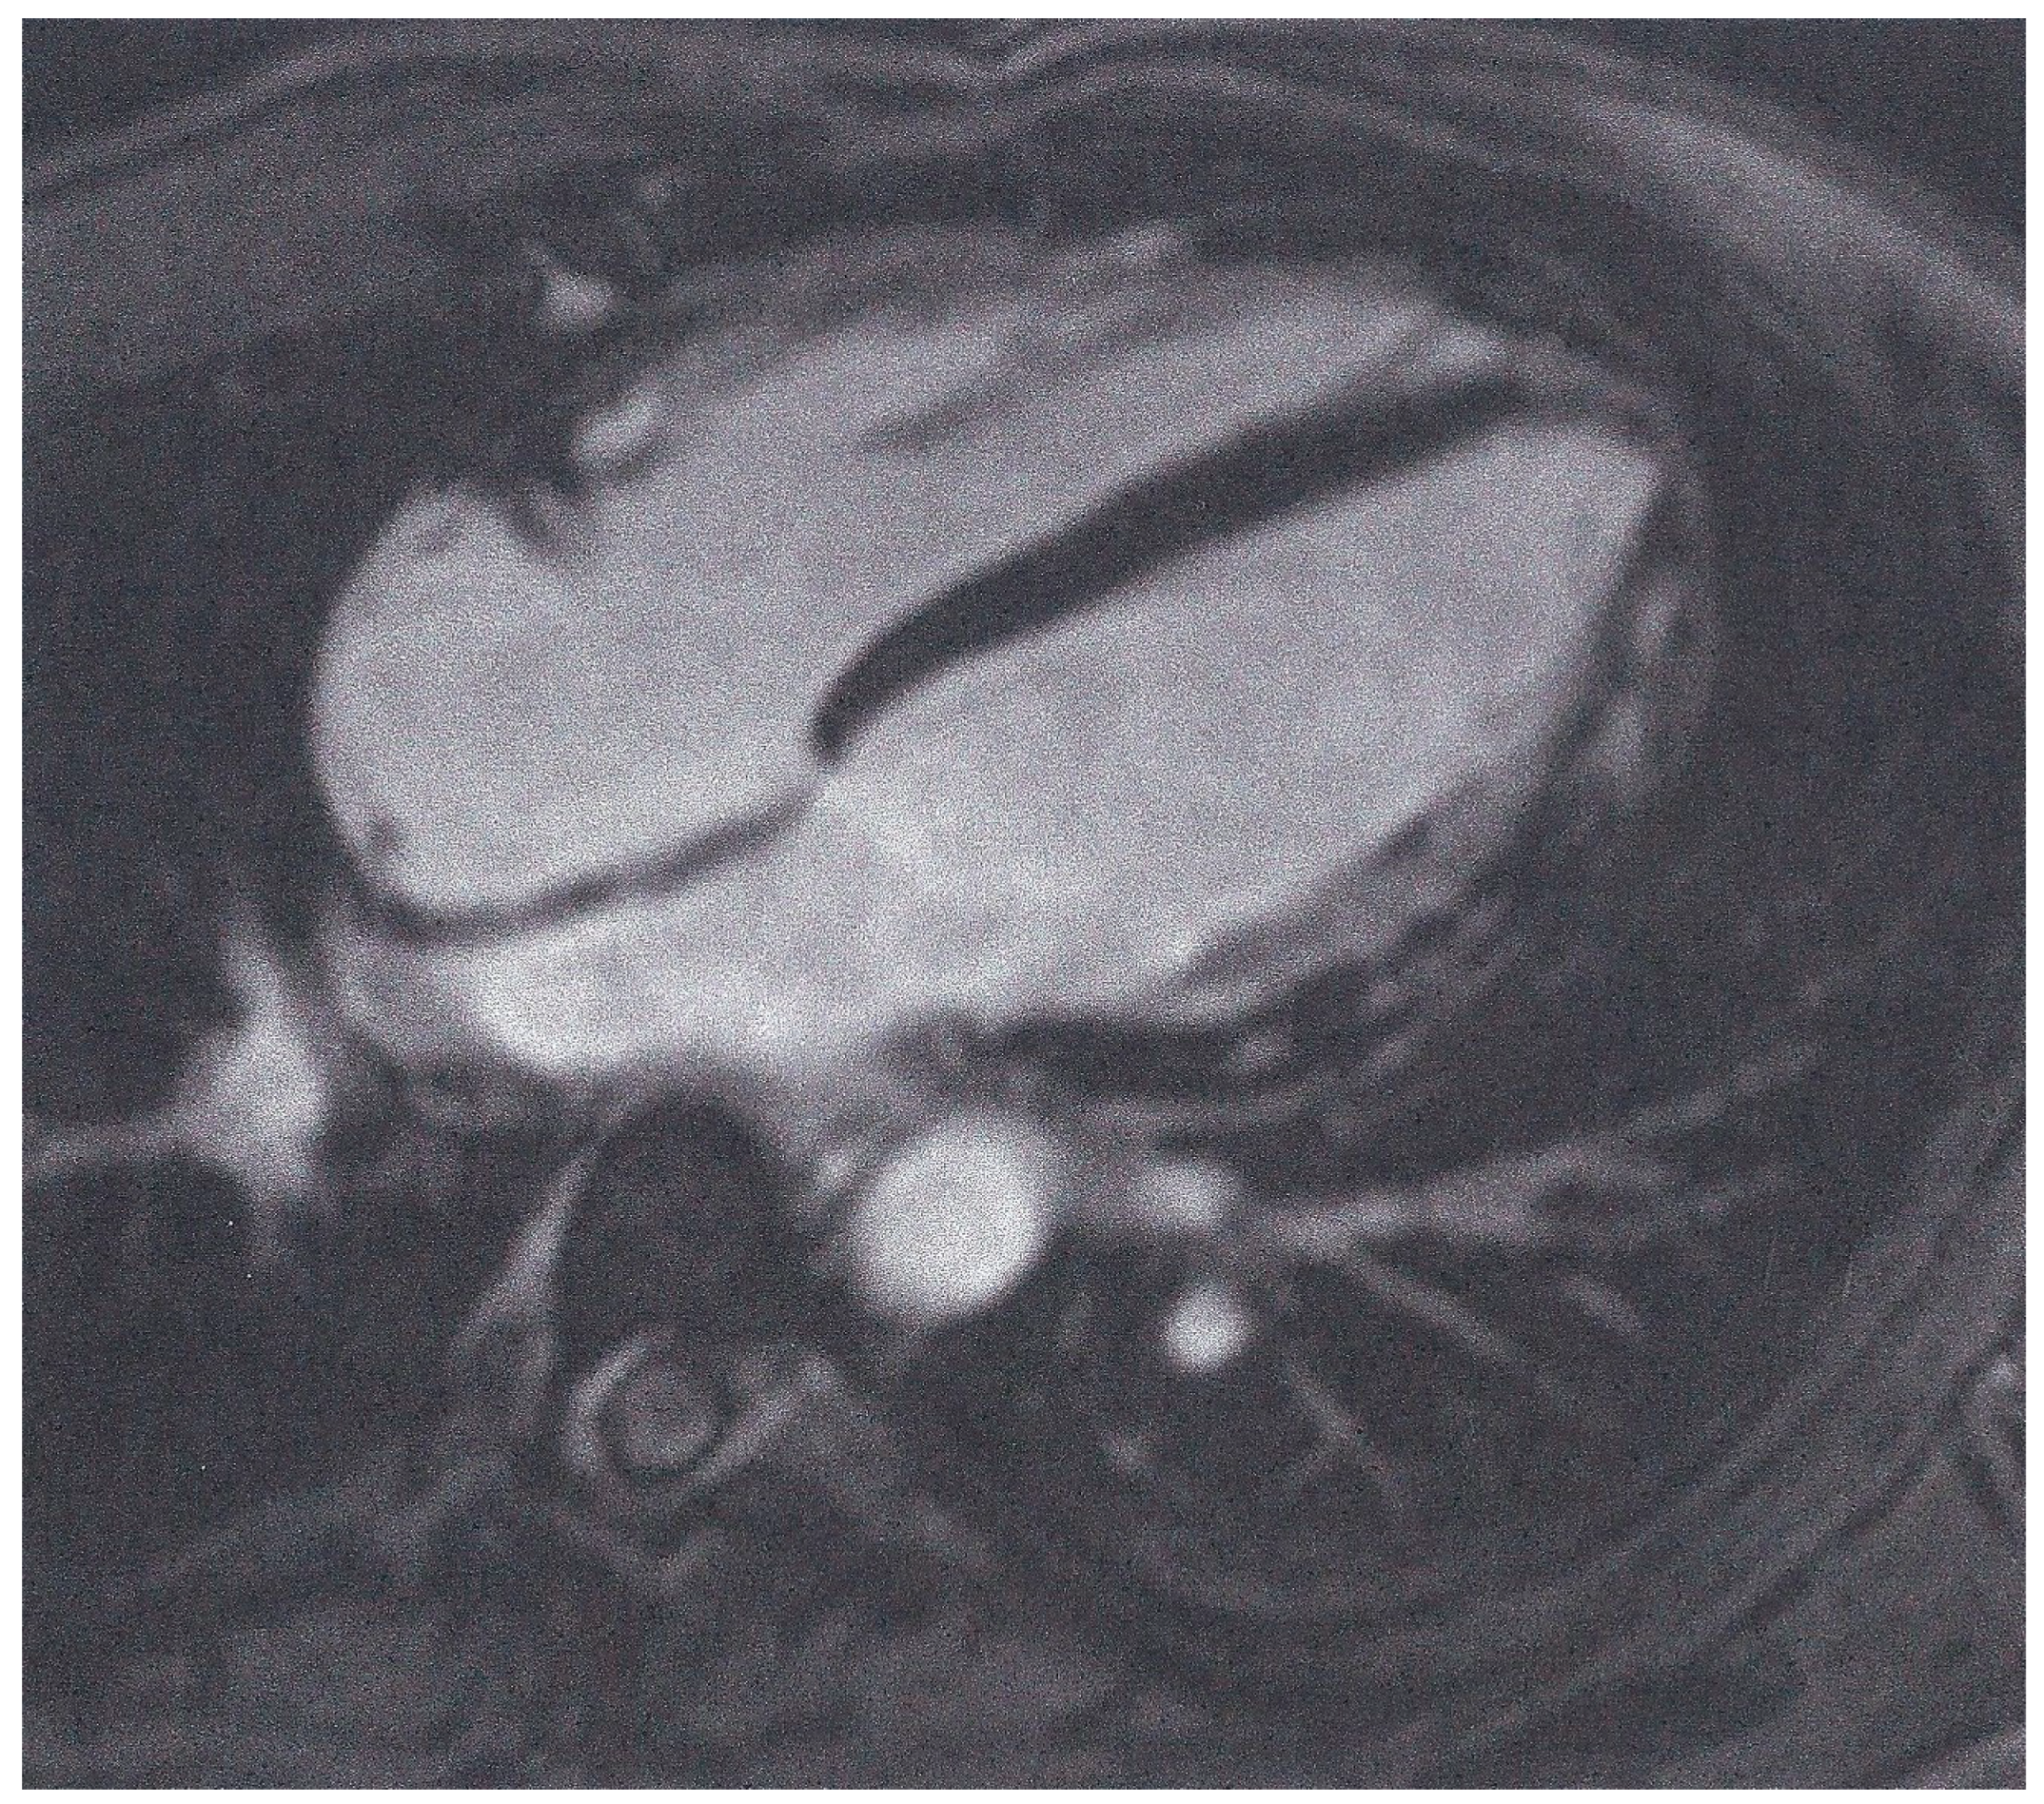

| Non-ischemic LGE | 149 (86%) |

| ≥1 pathologic T1 index | 141/145 (97%) |

| ≥1 pathologic T2 index | 62/173 (36%) |

| Both positive T1- and T2-criterion | 48/145 (33%) |